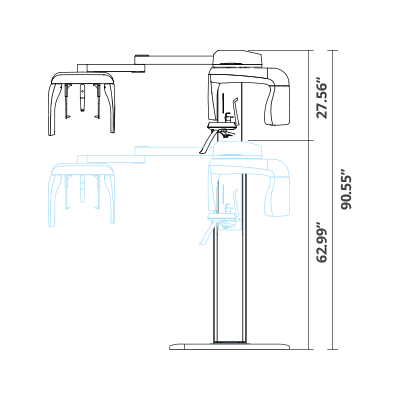

| TYPE | TOP VIEW | FRONT VIEW |

|---|---|---|

|

PaX-i SC (Pano/Scan Ceph) |

|

|